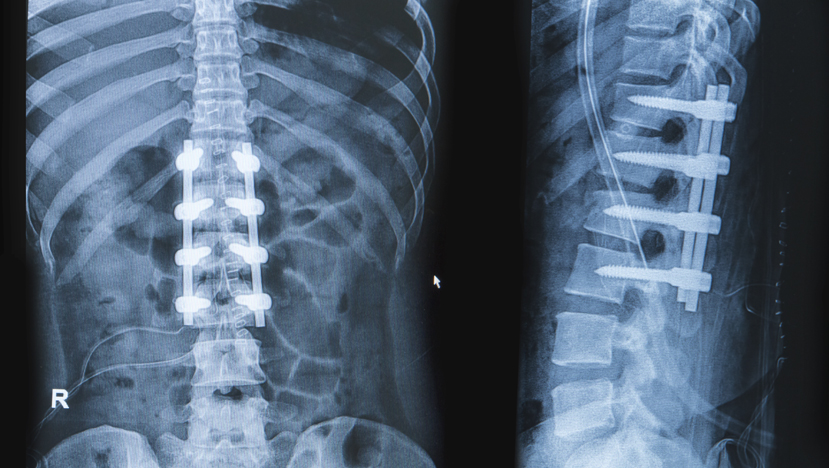

The surgeon will likely choose to use a combination of the patient’s own bone along with bone substitutes for fusion. The patient’s bone may be harvested from areas already exposed in the surgery (known as local bone grafts) or from other areas (such as the pelvic bone) through a separate incision. In addition to instrumentation (screws and rods), the surgeon may use certain implants made from surgical plastics, ceramics, or metals such as titanium.

The bone grafts, instrumentation, and implants are placed in very specific areas of the spine that ultimately result in complete bone fusion of the affected segments. This ultimately prevents motion, instability, and therefore, pain.